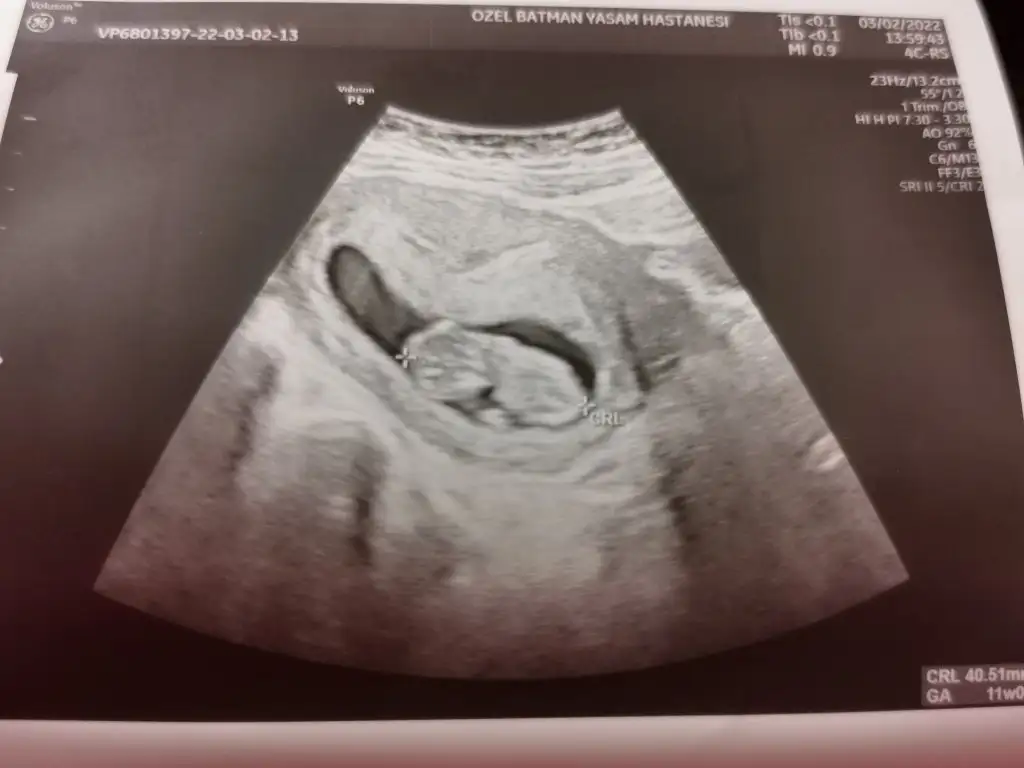

Erkek sankiMerhaba arkadaşlar benim için de tahmin yapabilir misiniz rica etsem 13+4 doktor bir tahminde bulundu ama emin olamadı. Sizin yorumlar nelerdir acaba

Daha önce de sormuştum ikra meyra hanıma ona erkek görünüyor dedi ama doktor kıza benziyor dedi emin olamadı ama burda kime sorduysam erkek gibi dedi. 2 kızım var bu 3. Bebeğim gönül olmayanı istiyor ama herseyin başı sağlık sağlıklı olsun da ne olursa olsun. Tabi merak işte. İnsan merakına yenik düşüyor. Çok teşekkür ederim yorum içinErkek sanki

İki hafta sonra gidecem doktora ozman netleşir.Daha önce de sormuştum ikra meyra hanıma ona erkek görünüyor dedi ama doktor kıza benziyor dedi emin olamadı ama burda kime sorduysam erkek gibi dedi. 2 kızım var bu 3. Bebeğim gönül olmayanı istiyor ama herseyin başı sağlık sağlıklı olsun da ne olursa olsun. Tabi merak işte. İnsan merakına yenik düşüyor. Çok teşekkür ederim yorum için